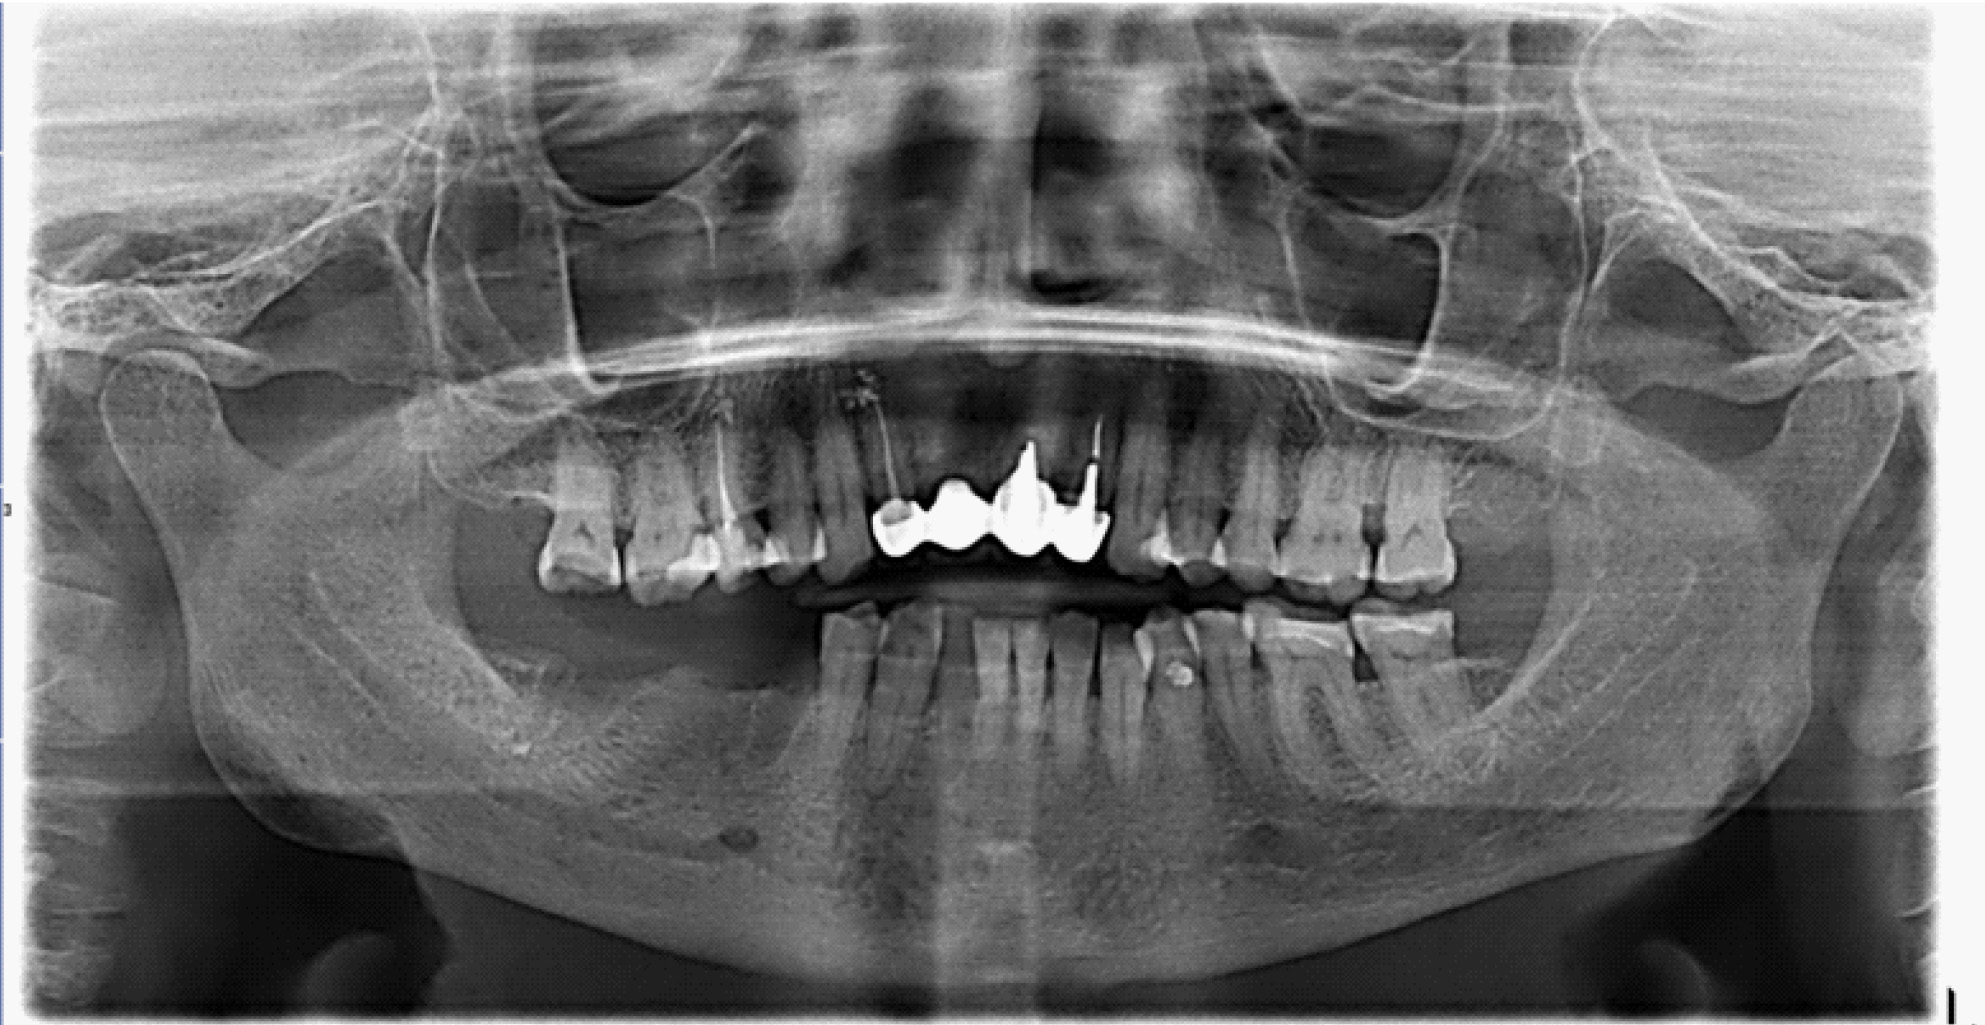

В полости рта: нарушение целостности слизистой оболочки полости рта, субтотальный остеонекроз альвеолярной части нижней челюсти слева. Вид костной тканей серо-коричневого цвета, пальпация безболезненная. На ортопантомограмме отмечается ограниченный участок деструкции костной ткани нижней челюсти с поражением тела нижней челюсти. Одонтогенной причины заболевания нет (рис. 1).

Рис. 1. Клинические проявления бисфосфонатного остеонекроза нижней челюсти во фронтальном отделе

Пальпация безболезненная. На ортопантомограмме определяются лунки зубов 4.7, 4.5 без явных признаков секвестрирования (рис. 3).

Рис. 3. Ортопантомограмма на этапе лечения остеонекроза нижней челюсти справа у пациентки Б. в 2022 г.